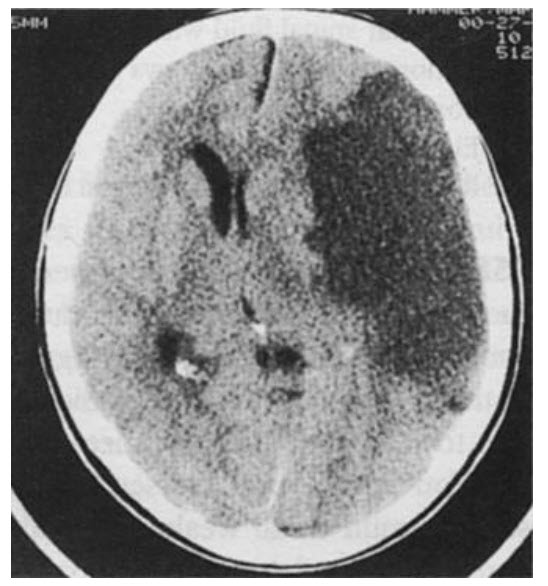

. A 68-year-old man with a history of hypertension and coronary artery disease presents with right-sided weakness, sensory loss, and an expressive aphasia. Neuroimaging studies are shown below. In the emergency department the patient’s blood pressure is persistently 160/95.

Although hypertension is an important cause of stroke, it should not be aggressively treated in the setting of acute cerebral ischemia. Since cerebral autoregulation is disrupted in acute stroke, a drop in blood pressure can decrease perfusion and worsen the so-called ischemic penumbra. Generally, blood pressure elevation up to 185/110 is not treated. Some stroke specialists recommend more aggressive blood pressure control in acute intracranial hemorrhage, but this patient has an ischemic (not hemorrhagic) stroke. Mannitol is of minimal benefit in cerebral edema associated with acute stroke.